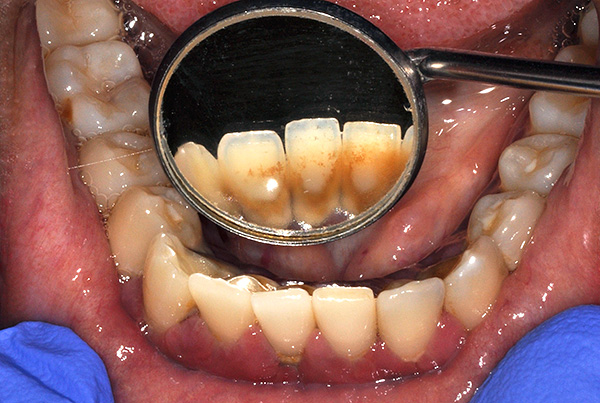

- Má higiene bucal;

A falta de higiene bucal causa acúmulo de placa e pedra nos implantes instalados, interrompendo a fixação gengival e provocando processos inflamatórios. Em tal situação, seus próprios dentes geralmente se tornam móveis no contexto da periodontite, e os implantes também "entendem" completamente.